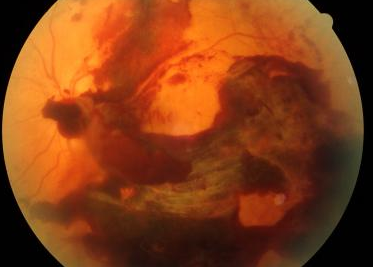

Central retinal vein occlusion - who gets it, S & Sx, & Rx. * Thrombus of central retinal vein obstructs outflow of BD -> ^intravascular pressure. * Dilated veins, retinal haemorrhage, cotton wool spots, retinal oedema (see following slide). * Sudden, painless, monocular vision loss ('like a curtain closing' - occuring in seconds). * Risk factors - age (>60 YO), HT, CVD, DM, glaucoma, hypercoagulability. * Rx - anti-VEGF, retinal laser. From lecture: https://www.dropbox.com/home/P-Year%20Surgical%20Lectures?preview=Ophthalmology+notes.pdf

Central retinal vein occlusion. K & C p1063